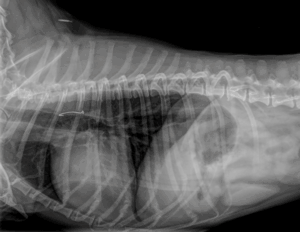

Het is belangrijk dan naar de dierenarts te gaan om röntgenfoto’s te laten maken om te kijken waar de vishaak zich bevindt en hoe deze het best verwijderd kan worden. In sommige gevallen is dit mogelijk via endoscopie (kijkoperatie). Echter soms zit de haak zo diep of zo vast dat het niet mogelijk is deze middels endoscopie te verwijderen en moet dit operatief gebeuren.

Vishaak in de slokdarm – zeer dicht bij luchtpijp en grote bloedvaten. Succesvol verwijderd door middel van endoscopie bij het MCD.